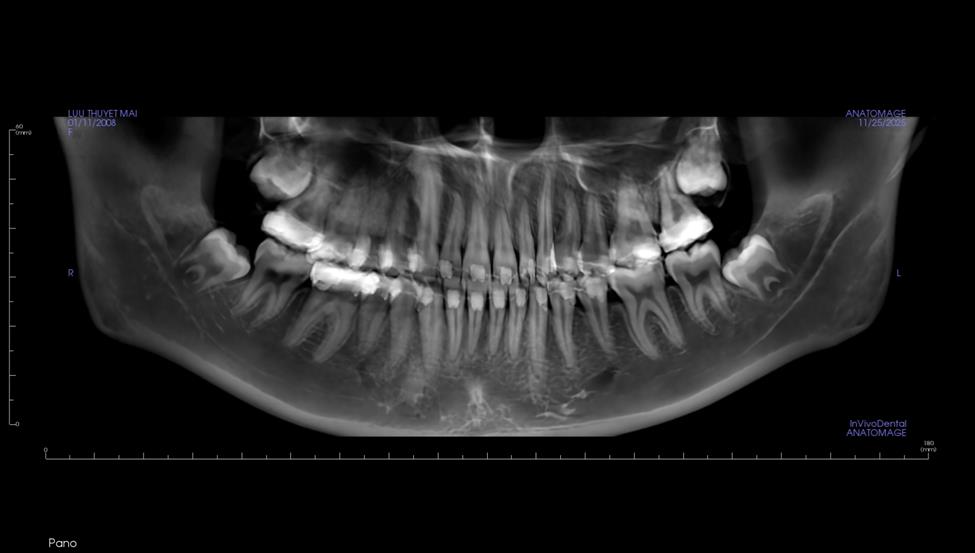

Trên phim X-quang, người bệnh có 4 răng khôn mọc lệch cần nhổ - Ảnh: BSCC